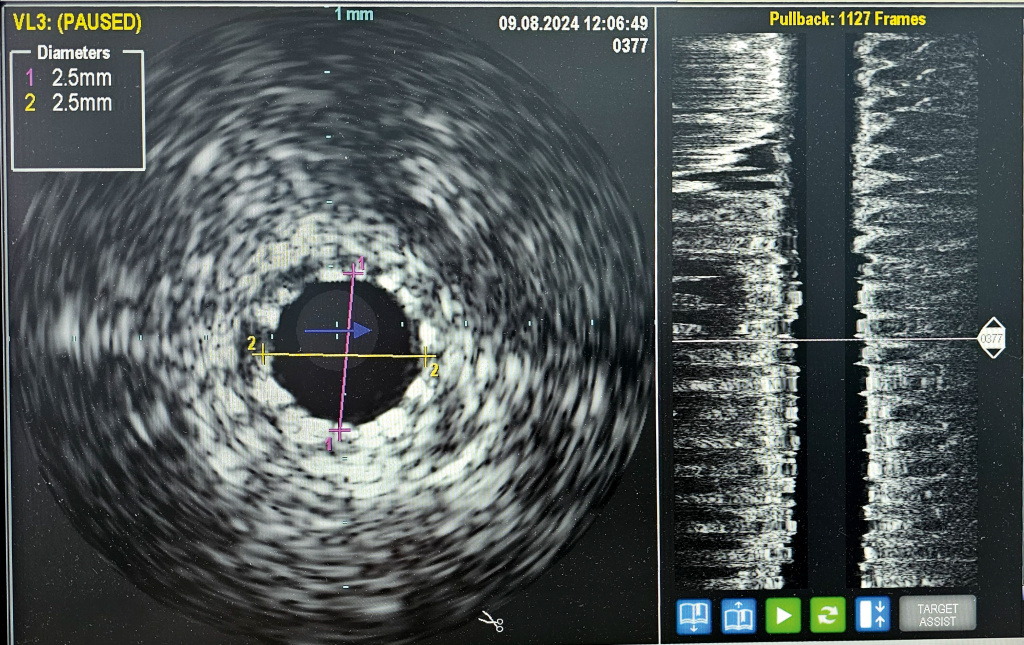

«Расширенный функционал современных ангиографических комплексов позволяет нашим эндоваскулярным хирургам выполнять весь спектр рентгенохирургических операций. Ежегодно в режиме 24/7 врачи проводят до 2,5 тысячи сложных вмешательств. Благодаря дополнительному оснащению теперь они могут действовать с высочайшей точностью. Внутрисосудистое исследование проводится при помощи специально разработанной системы доставки диаметром около 1 миллиметра с прикреплённым к ней миниатюрным ультразвуковым датчиком. Процедура не требует дополнительного оперативного вмешательства и позволяет в мельчайших деталях “рассмотреть” стенки поражённого сосуда изнутри», – отметил главный врач Городской клинической больницы имени М. П. Кончаловского, кандидат медицинских наук Алексей Погонин.

Дополнительная диагностика при помощи внутрисосудистого ультразвука позволяет в точности рассчитать площадь просвета артерии, визуализировать атеросклеротические бляшки и оценить их морфологические характеристики: где находятся, из чего состоят, насколько кальцинированы или фиброзированы, стабильны или нестабильны.

Исследование выполняется во время диагностической коронароангиографии и в руках опытного специалиста не занимает много времени. По проводнику миниатюрный датчик заводят в просвет коронарных артерий за место изучаемой области, где есть сужение, стент и т. п. Затем под рентген-контролем врачи вручную либо при помощи специального устройства медленно производят обратное подтягивание датчика к устью артерии, визуализируя её изнутри на всём протяжении. Специальный аппарат, к которому подключен УЗ-датчик, проводит количественный и качественный анализ полученного изображения и в реальном времени выводит данные на экран.